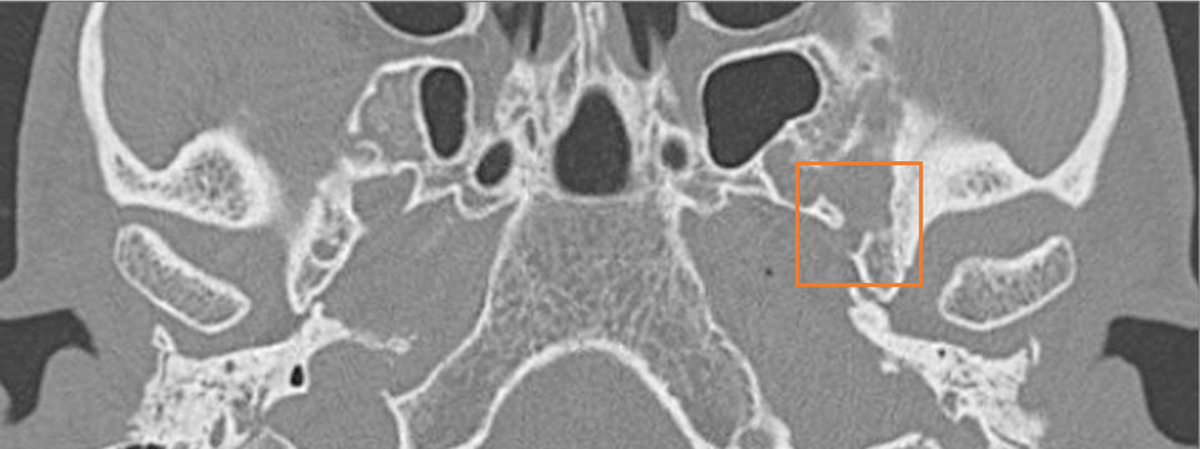

Figure 3

Axial CT scan showing the absence of the left foramen spinosum.